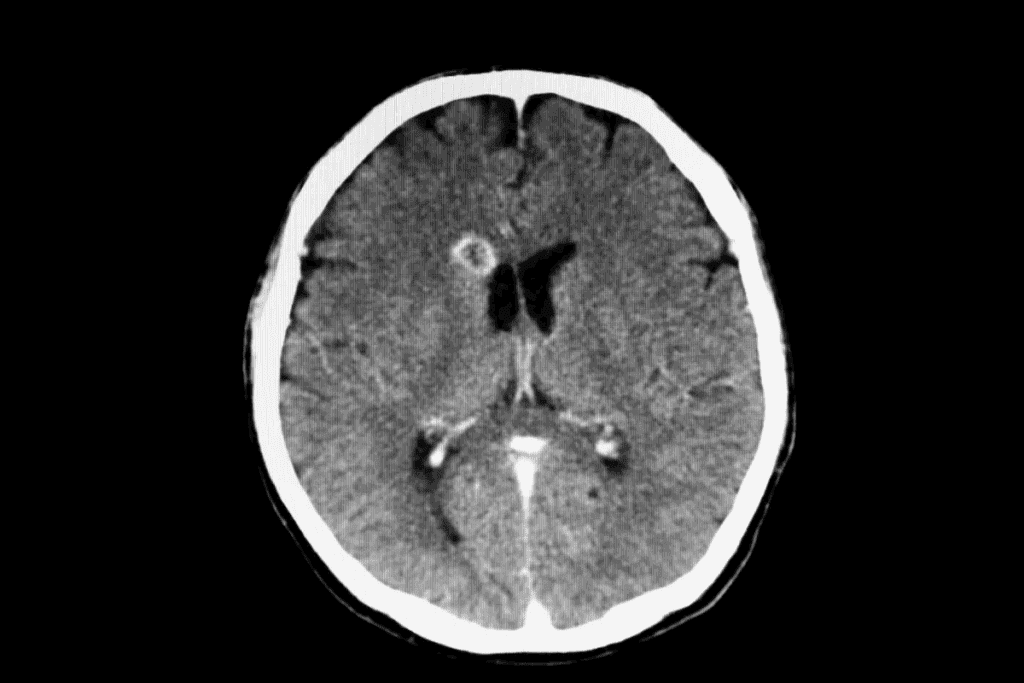

Imaging Techniques

Imaging techniques are vital for spotting brain lesions. The main ones are:

- Computed Tomography (CT) scans: CT scans give quick, detailed views of the brain. They help find lesions, bleeding, or other issues.

- Magnetic Resonance Imaging (MRI): MRI gives detailed images of the brain. It’s great for figuring out what kind of lesion it is, where it is, and how it affects the brain.